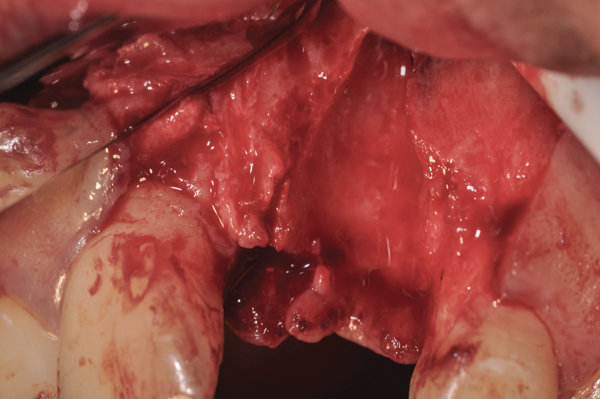

Fig 10. At 3 months postoperative, the flap was elevated demonstrating a restored buccal plate of bone.

Figure 10

Fig 11. An implant was placed in regenerated bone.

Figure 11